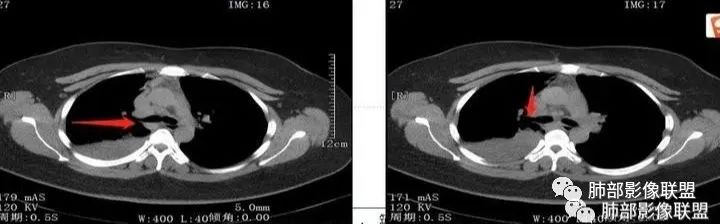

CT扫描示右肺下叶支气管堵塞,类圆形大肿块伴胸膜下大片肺实变影,增强扫描类圆形肿块延迟强化,见少量坏死,余实变区增强可见内部血管走行。纵隔见肿大淋巴结。考虑为恶性病变伴右肺下叶肺不张 医学百科网 | YxBaike.Com

患者青年女性,发热6 天,咳嗽、咳痰3天。为黄脓痰。胸部CT:右肺体积稍小,右中间支气管肿物堵塞,中叶、下叶大片实变不张,与正常肺组织分界清楚。增强实变影明显强化,右下肺支气管近心端见类圆形强化结节影,血管纤细,部分支气管显影变细,纵隔淋巴结肿大。结合无呼吸困难症状,病程长。综合考虑低度恶性病变并阻塞性肺炎,类癌可能大,鉴别结核、淋巴瘤。 医学百科网 | YxBaike.Com

关键点——中间段支气管堵塞处 医学百科网 | YxBaike.Com

通过视频显示中间段堵了

支气管腔内占位

远端低强化,提示粘液很多 医学百科网 | YxBaike.Com

本病例特点是中叶病灶和下叶病灶不一样,支气管腔内的病灶又是怎么样的呢?我们要是有沿支气管重建的冠状位、矢状位会更有利于分析。第一,中叶病灶明显粘液样改变、低密度,且低密度区有占位效应、膨隆,确实要考虑粘液表皮样癌。第二,中叶和下叶支气管显示不出来,但血管显示出来了。中叶病灶血管稀疏、细小,下叶病灶血管粗大、走形正常。朝外肺不张实变,不是单纯的肺不张,肺不张一般体积明显缩小、血管聚拢,该病例肿瘤于其中成分不一样,所以上叶部分病灶考虑为下叶病灶占位效应及膈面向上推压引起,中叶萎缩。综合腔内堵塞、纵隔淋巴结肿大要考虑恶性。

1.年轻女性,发热6天,咳嗽咳痰3天。高热伴腹泻。 医学百科网 | YxBaike.Com

2.右肺中下叶大片实性密度影,体积有缩小,密度不均,不均匀强化,前份可疑小范围液性密度区。

3.中间段支气管阻塞,腔内隐约见息肉样结节或突入,结节有较明显强化,这很重要,说明它有生命力,强烈提示新生物,而非分泌物或异物等等。

可惜腔内腔外混沌一片,我们不能分辨管壁及管壁外细节,我们不能判断新生物实际大小,不能判断局部支气管彻底破坏还是结节影跨越腔内外。 医学百科网 | YxBaike.Com

4.年轻、女性,支气管腔内相关新生物,会想到类癌或涎腺类肿瘤,如粘液表皮样癌等。强化较明显类癌可能性较大。支气管鳞癌和间叶组织肿瘤的可能性都非常小。